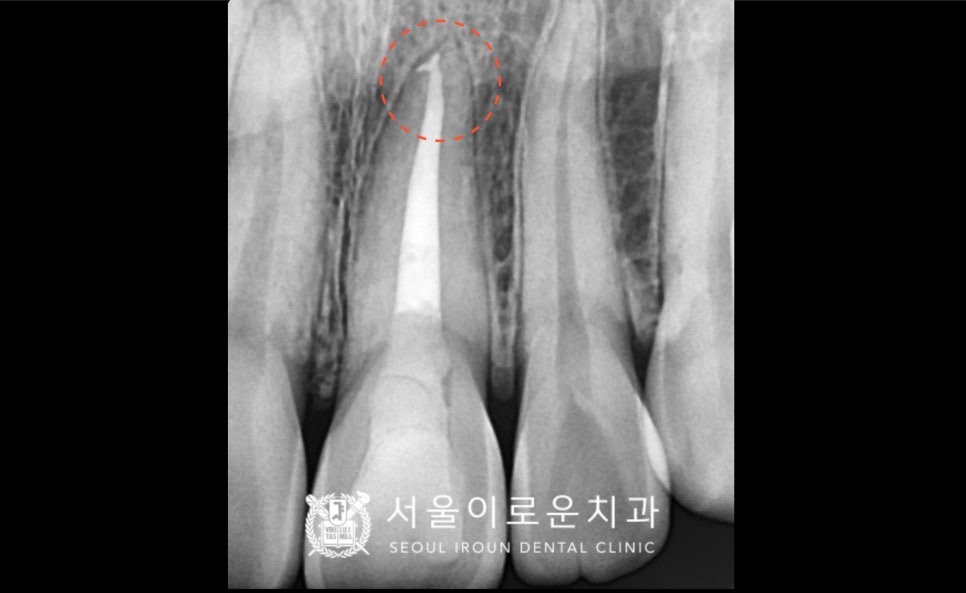

스탠다드 x-ray사진으로 확인한 결과

뿌리 끝까지 충전이 제대로 이루어지지 않아

재신경치료가 필요하였답니다.

꼼꼼하게 재신경치료를 진행하고,

뿌리끝까지 약제가 충전된 것을 확인한 뒤

실활치 미백을 2회 시행하였습니다.